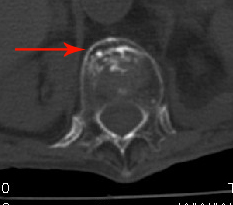

男:89岁因外伤后2天行ct检查。请各位战友讨论图中所指是否是骨折和形成该影像的原因(扫描层面位于椎体中份)。

老年性骨质疏松,椎体前缘出现双边征支持压缩骨折。椎体骨质稀疏,似有破坏,警惕溶骨性骨转移。

椎体前缘双边征,其后椎体内密度增高均提示压缩性骨折

椎体前缘呈双边征 考虑 压缩性骨折,椎体退行性病变。

我的报告1:腰椎骨质退行性改变。

2:t12改变考虑压缩骨折?请结合临床。